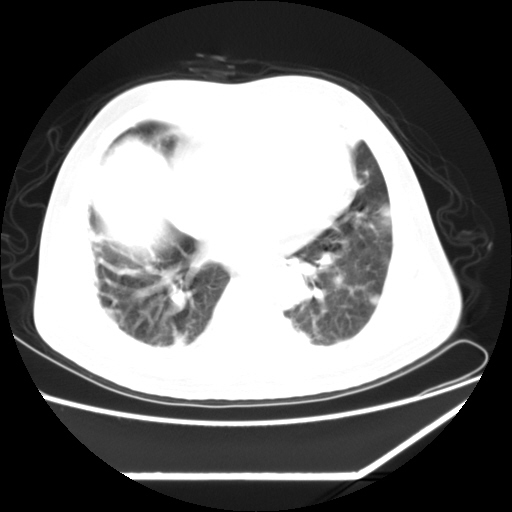

男,57,畏寒,发热

双肺多发结节样病灶,部分内见透光区,纵隔内见淋巴结肿大。结核临床如有畏寒,高热,白细胞增高首先考虑迁徙性肺脓肿(多是金黄色葡萄球菌感染)。

注意除外转移瘤。

1)考虑两肺感染性病变(金黄色葡萄球菌肺炎?);建议抗炎治疗后复查排除其他。2)双侧少量胸腔积液。

双肺典型的亚急性粟粒性肺结核

双侧胸膜结核